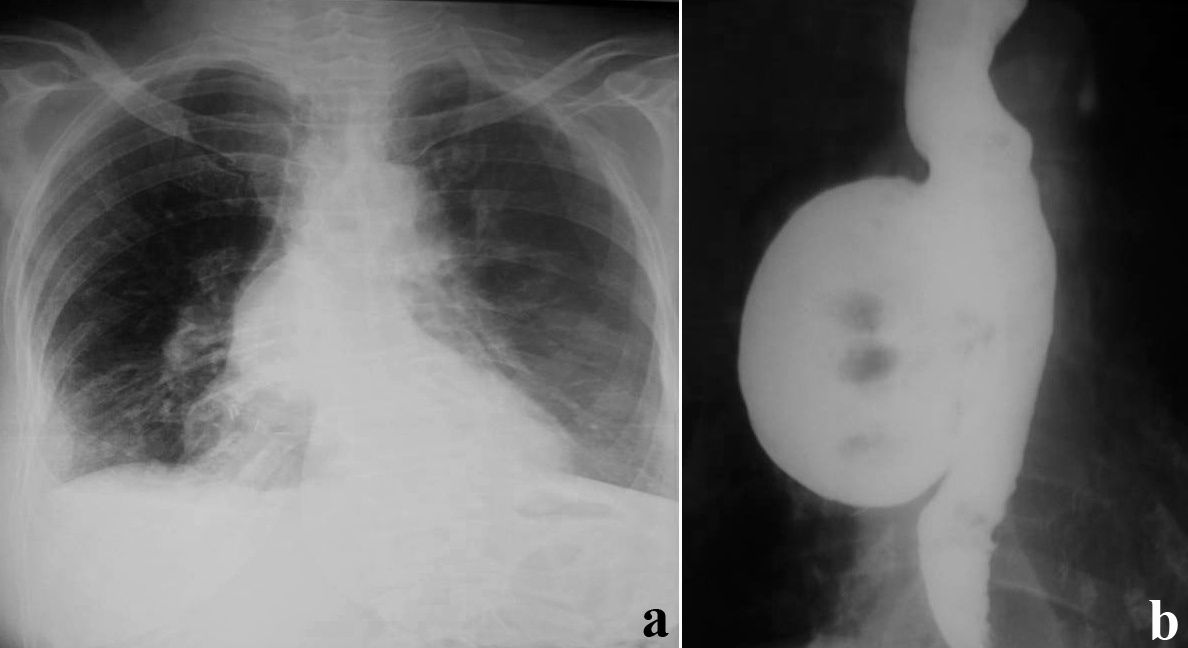

Esophageal Diverticulum Causes Types Symptoms Diagnosis Treatment

ESOPHAGEAL OBSTRUCTION Define Causes Symptoms Diagnostic

ESOPHAGEAL OBSTRUCTION Define Causes Symptoms Diagnostic